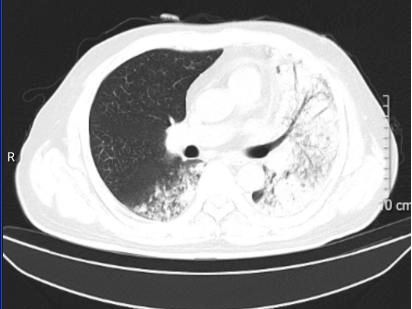

案例1:

一位孕晚期女性,因“发热4天、咳嗽1天”由外院转入该院ICU。初期在外院按流感进行了抗病毒治疗,但效果欠佳。转入ICU时已出现血压低、心率快、呼吸急促等休克表现。完善CT检查发现半个肺“全白了”,后经检测确诊为“鹦鹉热”,经针对性治疗后,这位孕妈已好转出院。

图片

治疗前

治疗后